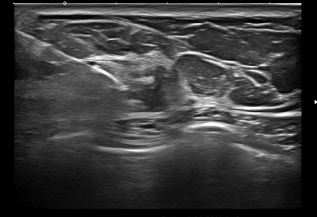

상기환자 외부병원 유방의 이상소견으로 정밀검사위해 내원하신 50대 여성분으로

우측유방 혹 총조직검사 시행해 유방암 진단되었습니다